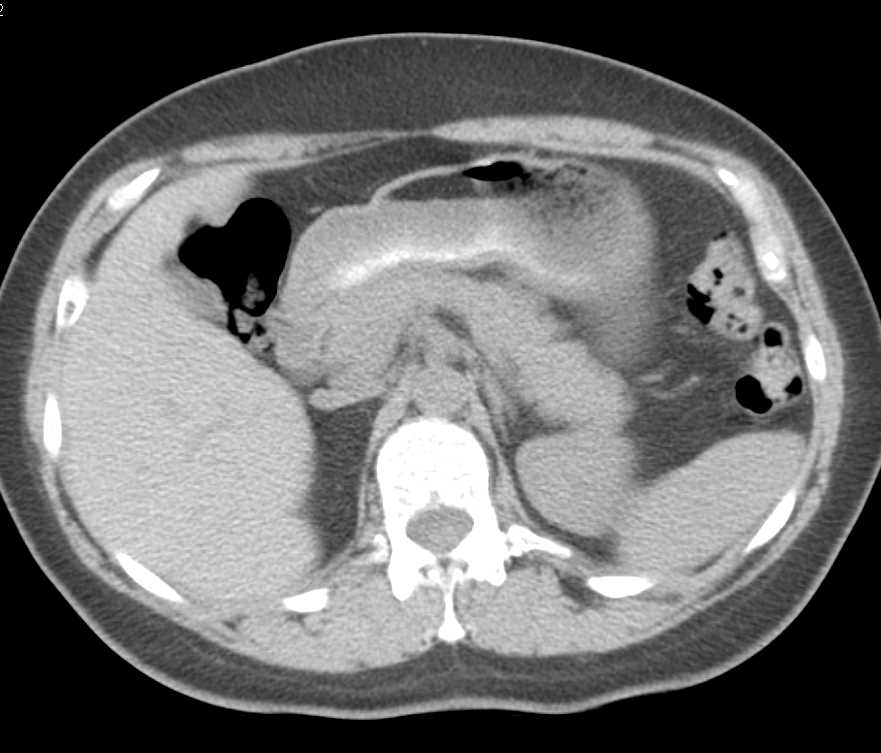

Infiltrating Gastric Adenocarcinoma